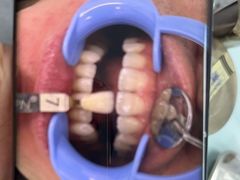

• 同步齿科·同富门诊·正畸种植口腔旗舰店(布吉店)

• -同步齿科·同富门诊·正畸种植口腔旗舰店(布吉店)

波比的发呆Life | 23-11-14